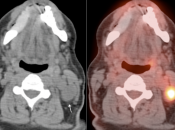

Unilateral FDG-Avid Tonsil (or Relative Increased Avidity of One Tonsil):

Special care is required when assessing the incidental finding of a unilateral hot tonsil (or relative increased uptake within one tonsil) — even though most unilateral hot tonsils are benign. Proposed techniques for assessment have included SUV threshold cutoff values, metabolic tumor volume assessment, and SUV ratios.

Unfortunately, it is advisable to raise at least a degree of concern for most FDG-avid unilateral tonsillar findings. The level of suspicion, of course, depends on the presentation.

At PETCTMD, we utilize the following practical approach for the incidental finding of a unilaterally FDG-avid tonsil:

- NON-ENLARGED AND:

- Unilaterally Avid (≥ Liver Uptake)

- OR

- Uptake “Unquestionably” > Contralateral Tonsil

We typically report, “While this uptake is typically physiologic or inflammatory in nature, direct visualization may be of diagnostic value, if clinically warranted.”

(If the uptake is < liver uptake, we presume the metabolic activity to be physiologic or inflammatory)

- UNILATERALLY ENLARGED AND:

We typically report, “While its increased size and increased metabolic activity may be inflammatory in nature, direct visualization may be warranted to exclude a neoplastic process in this case.”

- Any Unilateral Tonsillar Uptake Associated with Hypermetabolic Cervical Nodes:

Clearly, the presence of hypermetabolic cervical nodes dramatically increases the likelihood of malignancy (and the confidence of your reporting).